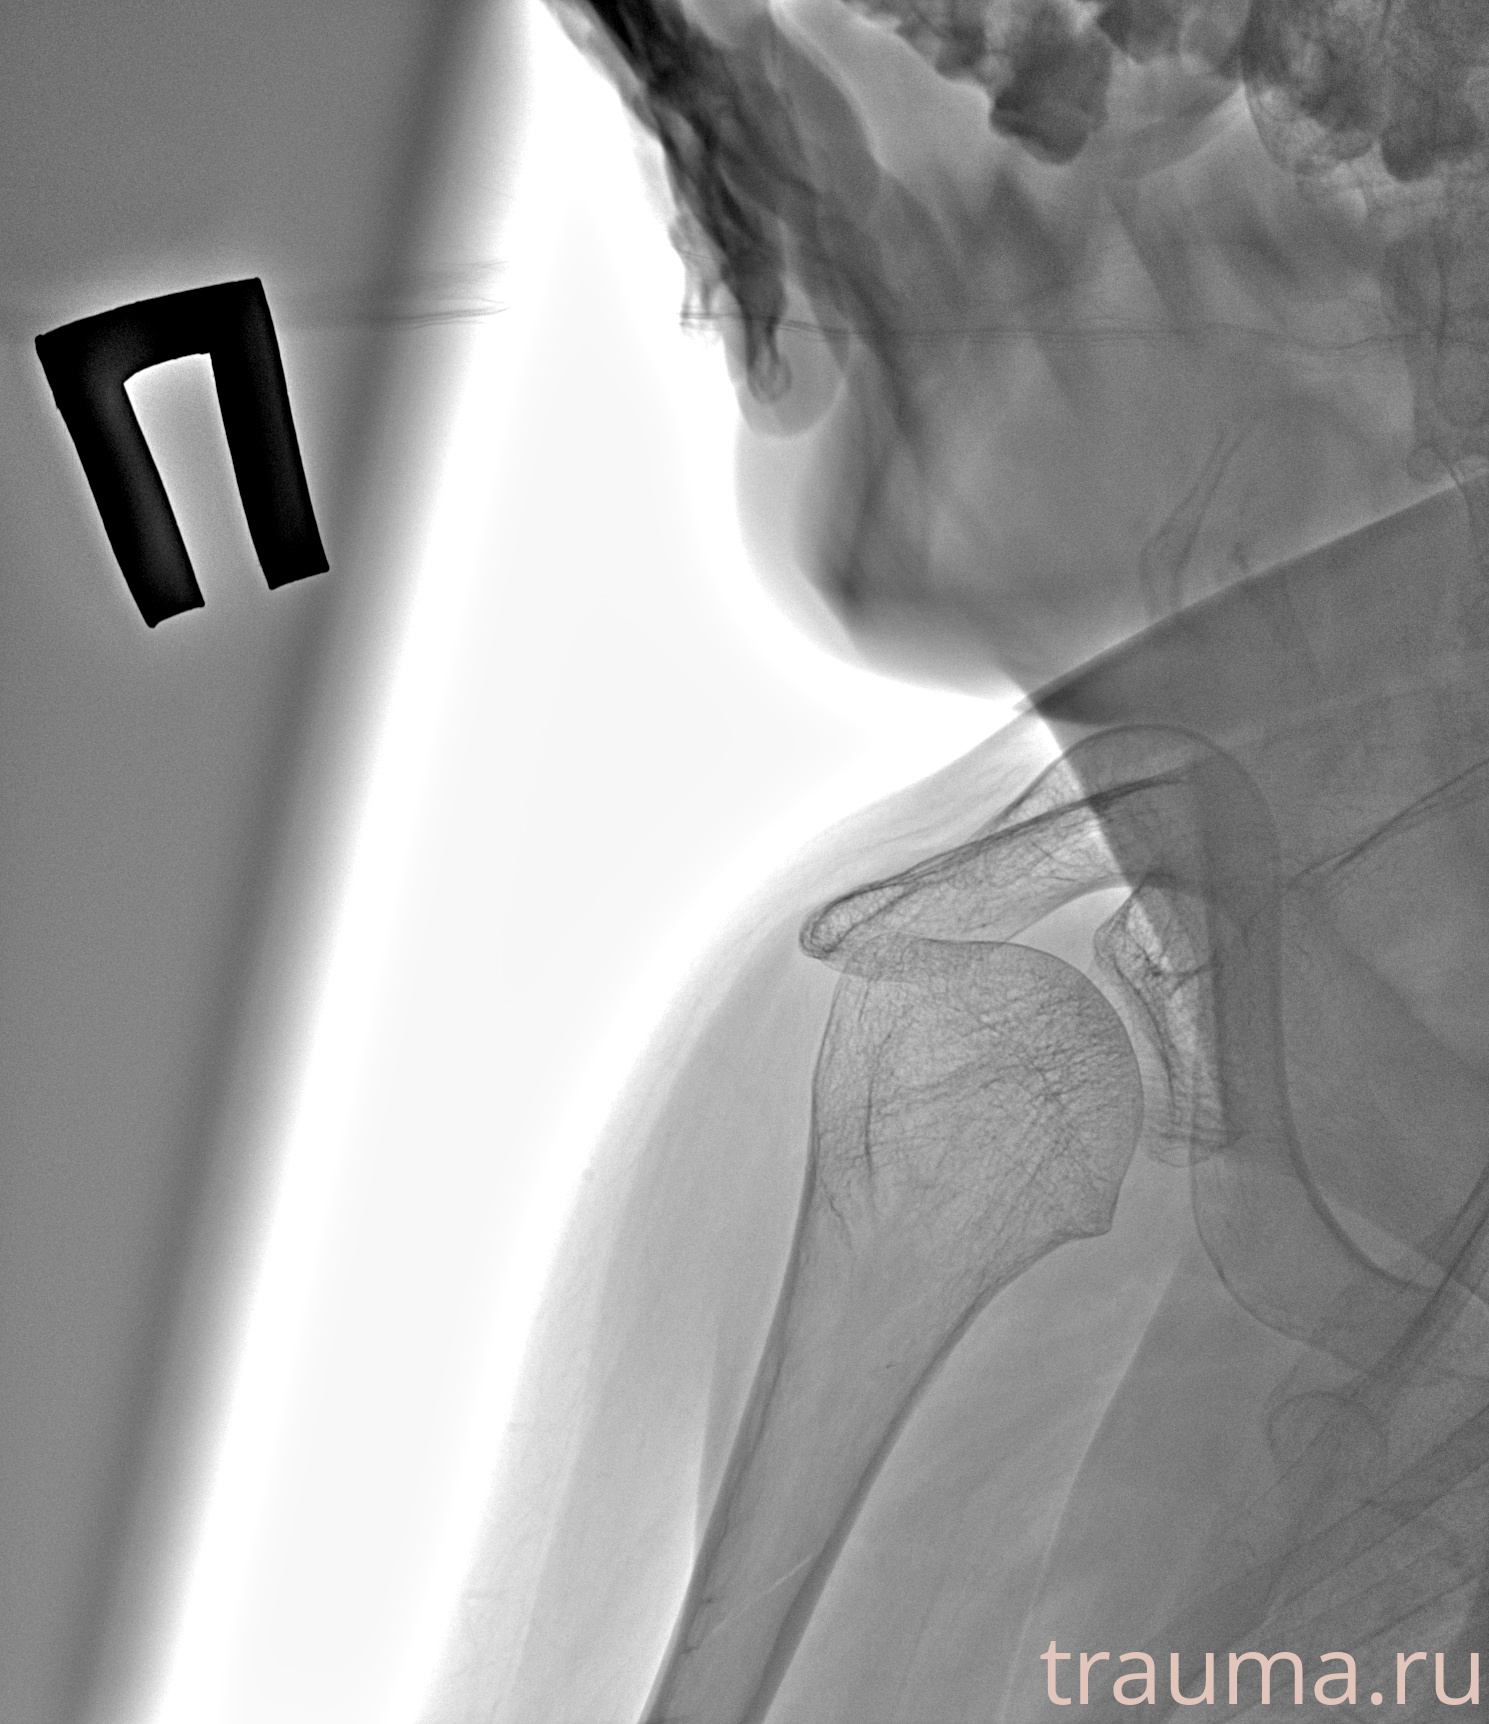

Рентген на дому: по вашему адресу приезжает врач-рентгенолог, травматолог-ортопед с мобильным рентгеновским аппаратом, проводит диагностику травмы или заболевания, делает необходимые рентгенограммы, дает рекомендации по дальнейшему лечению. Получить качественные снимки в домашних условиях возможно благодаря уникальной методике, разработанной МосРентген Центром для института  Склифосовского

при переломе шейки бедра и пневмонии от компании МосРентген Центр - партнера Института имени Склифосовского